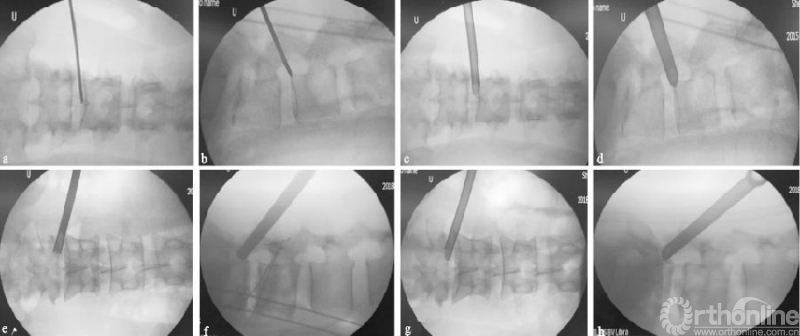

向上游离的腰椎间盘突出症由于没有上关节突的阻挡,一般通过水平穿刺或向上稍倾斜角度的穿刺,不需要行关节突成形,利用工作套管的活动度及带角度的髓核钳,可相对容易摘除椎间盘(见图4a-d);而对于向下游离的腰椎间盘突出症,要根据游离物的大小及方向,来行适当的关节突成形以扩大偏下方的椎间孔区,以顺利摘除椎间盘,减少残留可能(见图4e-h)。

游离型腰椎间盘突出症为椎间盘向上或向下脱垂,Fardon和Lee等[15-16]有详细的分型。在向下游离的突出中,有一个“隐蔽区”[17],该位置的突出可同时压迫到出行根和走行根。采用经皮椎间孔镜椎间盘切除术摘除游离型突出,一般有上关节突、椎弓根和椎板等骨性结构的阻档;如椎间盘为分散的块状、工作空间显露不足时,极易残留。因此,术前掌握椎间盘突出的具体位置、大小形态及其与神经根毗邻关系和经皮椎间孔镜椎间盘切除术的设计策略密切相关[18]。

(a)(b)L4/5节段向上游离型突出穿刺置管透视图,其中(a-b)为一级导杆定位图;(c)(d)工作通道放置图;(e-h)L4/5节段向下游离型突出穿刺置管透视图,其中(e-f)为保护套管下环锯行FP图;(g)(h)工作通道放置图

图4 L4/5节段游离型突出穿刺置管图

对于向下游离的腰椎间盘突出症,要相对靠尾端行关节突成形,经椎弓根上缘入路[19]、靶向穿刺[20],利用弹簧钳等工具来摘除椎间盘。以上入路适用于低位游离的或带有蒂部的椎间盘突出,但对于高位游离且分块的类型或者“隐蔽区”突出,则较难摘除干净;此时可通过关节突成形切除部分椎弓根上缘[21-22],向下扩大空间来摘除椎间盘。既往也有研究采用对侧关节突成形技术对患者椎间盘行定点清除术,对侧入路因其向下角度较大,“隐蔽区”同样适用,但此类手术方式有神经损伤的风险[23-24]。